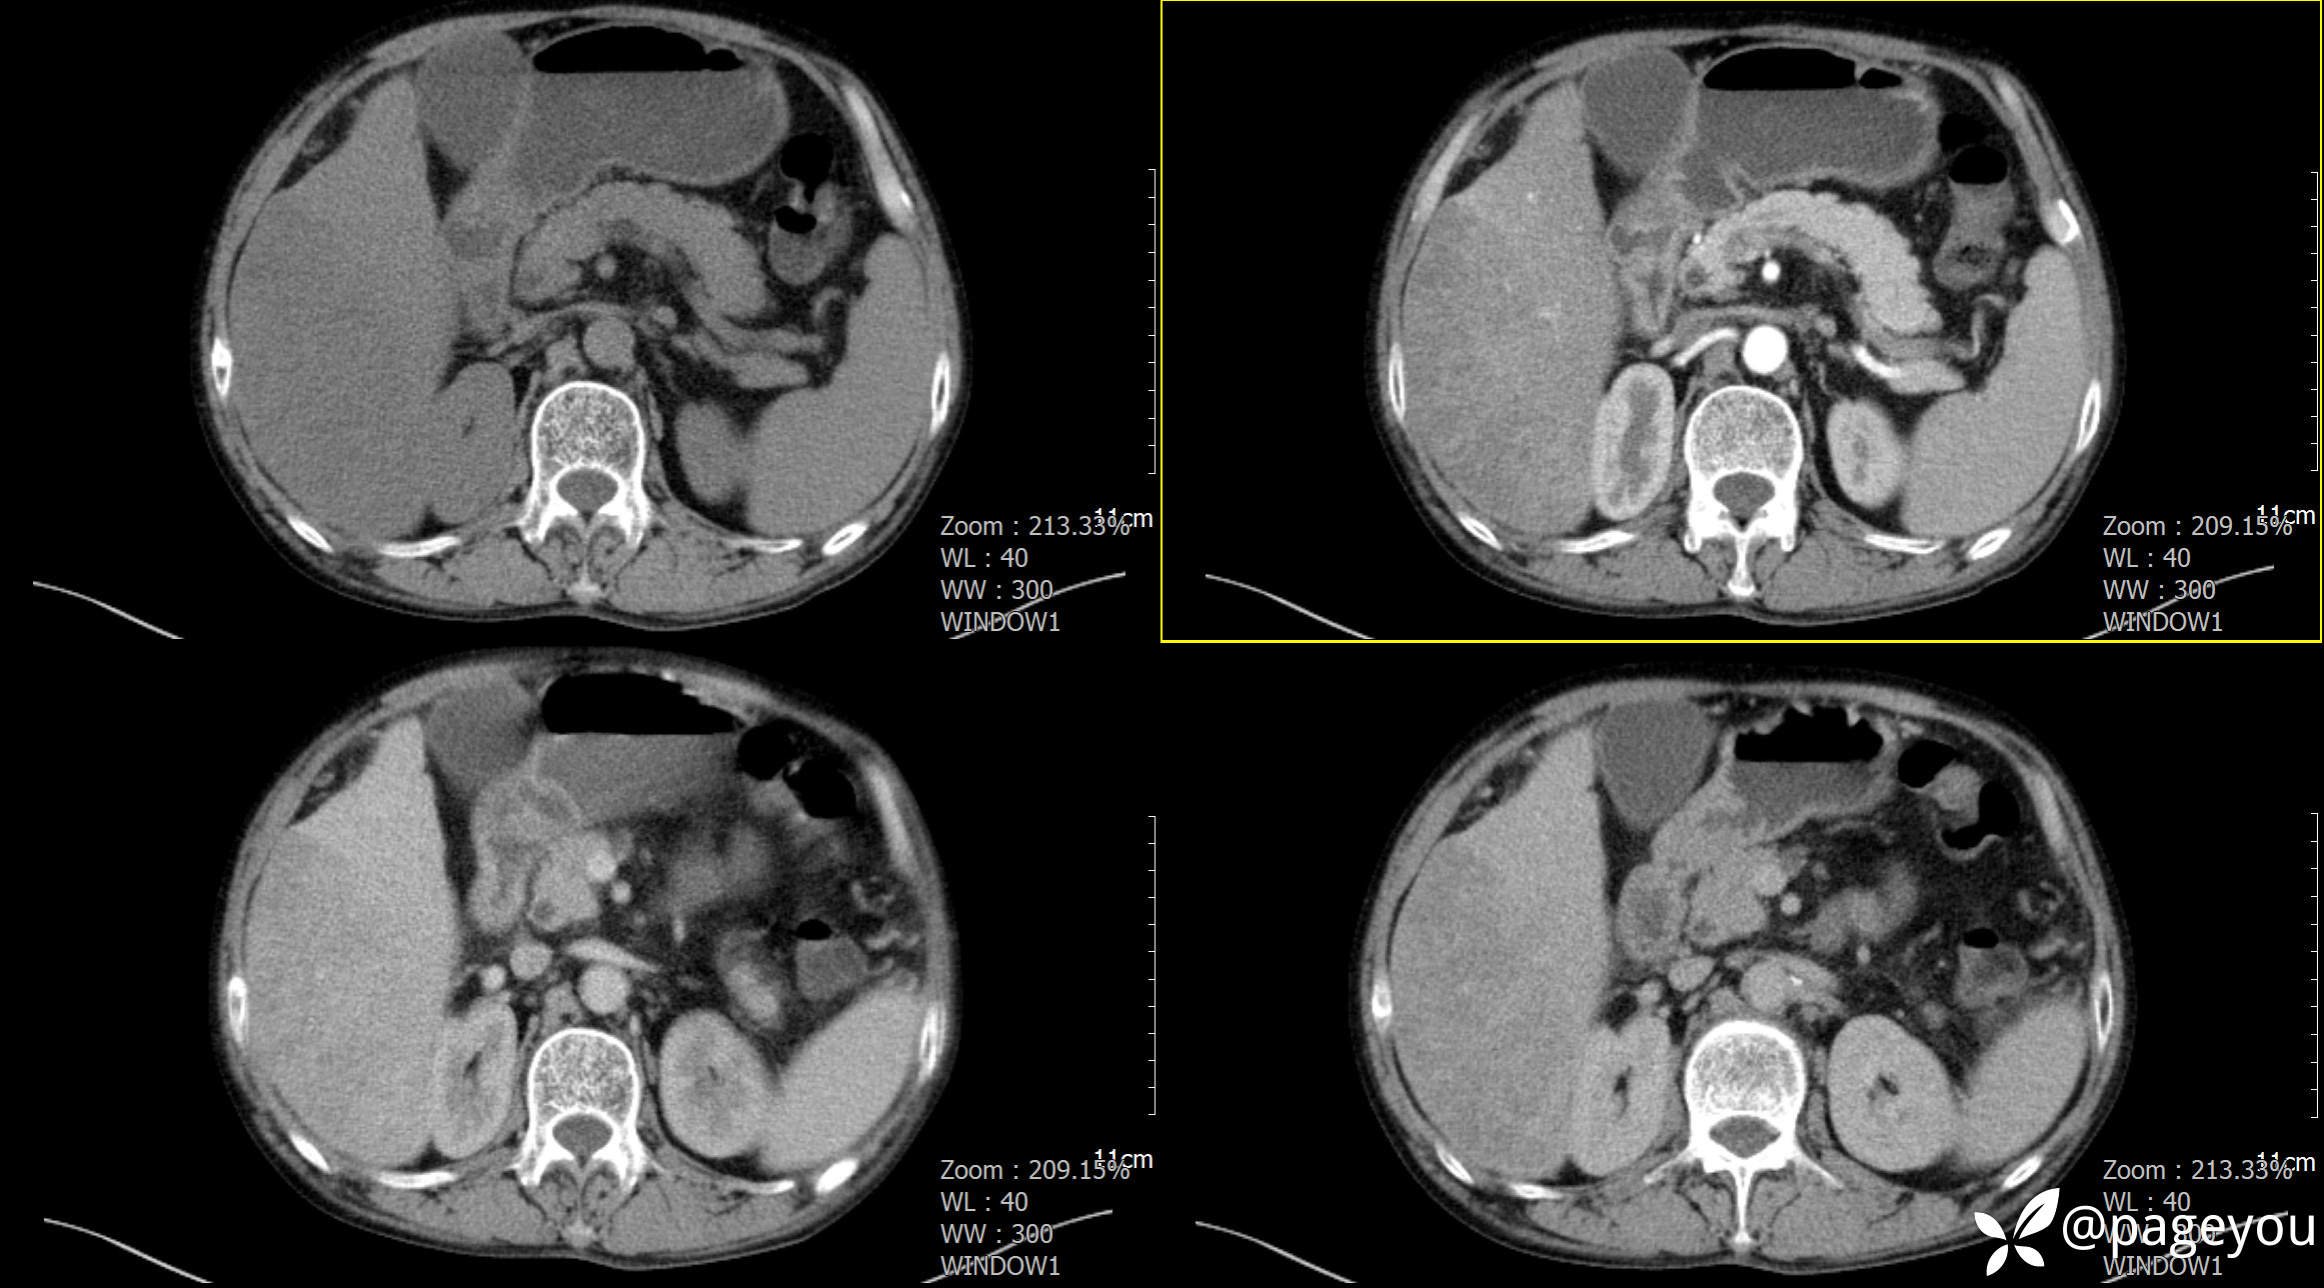

CT检查: